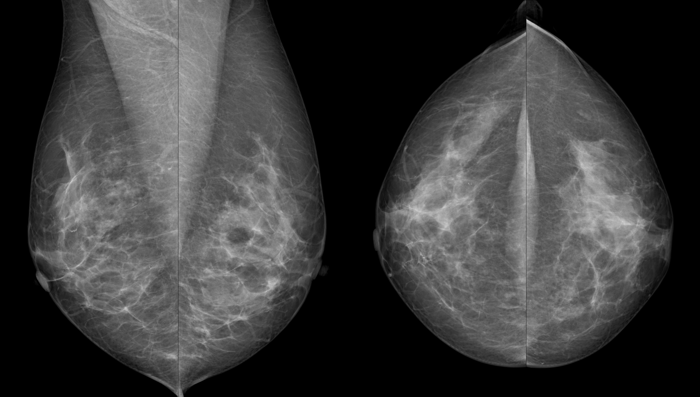

Von jeder Brust werden üblicherweise zwei Aufnahmen - jeweils von oben nach unten (cranio-caudale Aufnahme) und schräg von innen nach außen (medio-laterale oblique Aufnahme) - angefertigt. Die Brust wird dabei in eine Vorrichtung eingespannt und komprimiert:

Warum werden von jeder Brust zwei Aufnahmen gemacht?

Die Brust ist ein dreidimensionales Organ, die Aufnahmen sind hingegen flach. Um die sichtbaren Strukturen räumlich richtig einordnen zu können, sind daher zwei Aufnahmen in verschiedenen Ebenen notwendig.